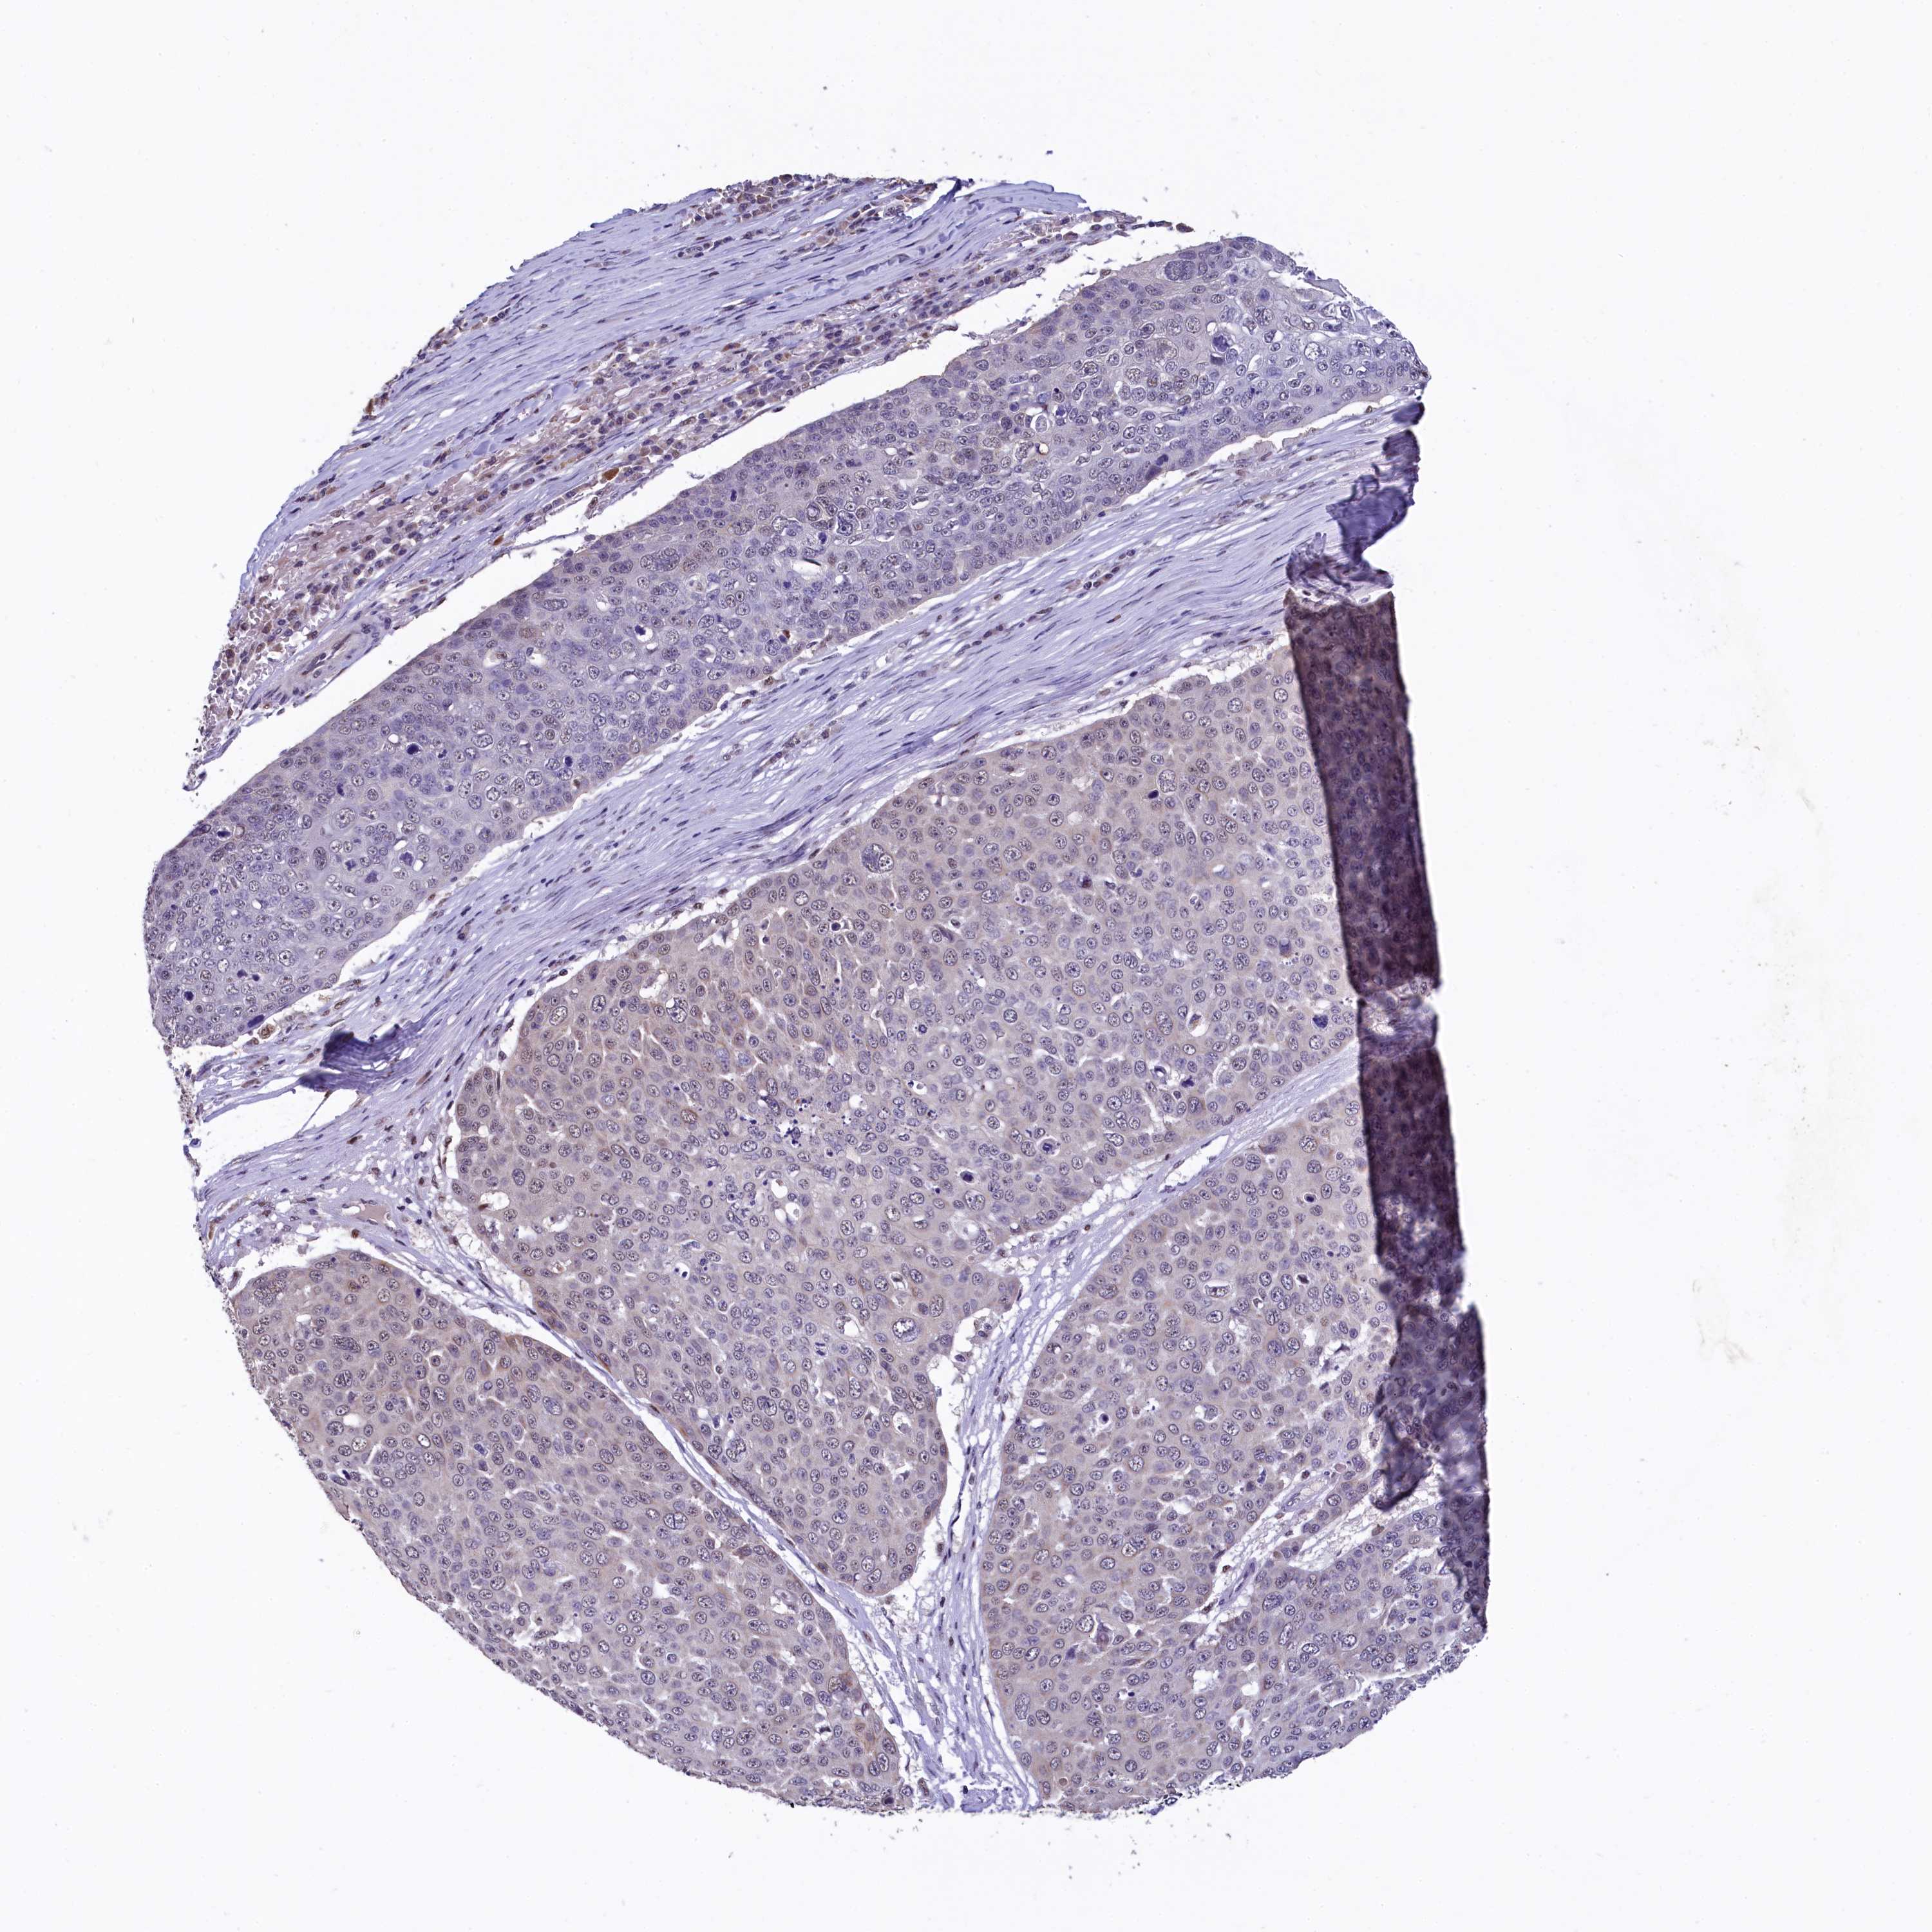

CANCER SKIN CANCER Show tissue menu

Basal cell and squamous cell cancer

SKIN CANCER - Protein expressioni

A mouse-over function shows sample information and annotation data. Click on an image to view it in a full screen mode. Samples can be filtered based on level of antibody staining by selecting one or several of the following categories: high, medium, low and not detected. The assay and annotation is described here.

Each image is clickable and will lead to virtual microscopy that enables deeper exploration of all samples and also displays staining intensity scores, fraction scores and subcellular localization as well as patient and tissue information for each sample.

Antibody HPA041062

Antibody HPA045473

Basal cell carcinoma

Squamous cell carcinoma, NOS

Squamous cell carcinoma, metastatic, NOS